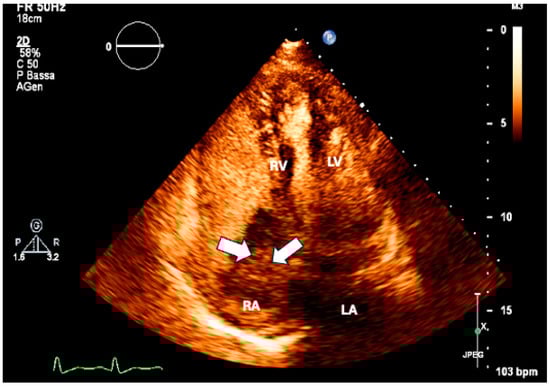

- L’Angiocola, P.; Donati, R. Cardiac masses in echocardiography: A pragmatic review. J. Cardiovasc. Echography 2020, 30, 5–14. (In English) [Google Scholar] [CrossRef]

- Aggeli, C.; Dimitroglou, Y.; Raftopoulos, L.; Sarri, G.; Mavrogeni, S.; Wong, J.; Tsiamis, E.; Tsioufis, C. Cardiac Masses: The Role of Cardiovascular Imaging in the Differential Diagnosis. Diagnostics 2020, 10, 1088. (In English) [Google Scholar] [CrossRef] [PubMed]

- Xia, H.; Gan, L.; Jiang, Y.; Tang, Q.; Zhang, P.; Tang, X.; Wen, L.; Liu, Z.; Gao, Y. Use of transesophageal echocardiography and contrast echocardiography in the evaluation of cardiac masses. Int. J. Cardiol. 2017, 236, 466–472. (In English) [Google Scholar] [CrossRef]